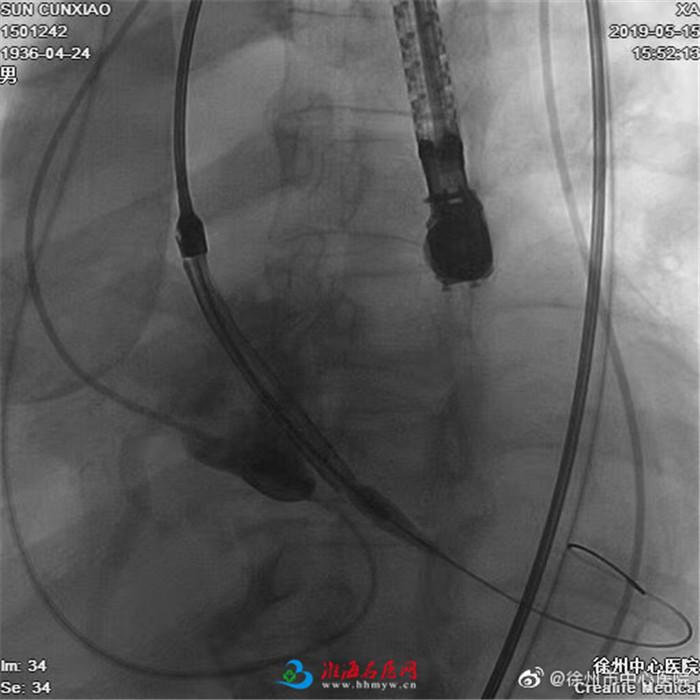

不同于传统的开胸换心脏瓣膜手术,TAVR是一种微创介入手术,不用开刀即可完成重度狭窄的主动脉瓣膜置换;入选的患者多是外科换瓣禁忌而且高危患者。本例患者高龄、血管穿刺入路难、二叶瓣、瓣膜钙化积分高、横位心、主动脉与左心室成角达70度,属于极高危患者。

为了保障这一心血管领域国际最高精尖介入技术的成功引进应用,市中心医院早在2年前就瞄准这一技术组建了包括心内科、心外科、麻醉科、心脏超声、心脏CT、导管室、ICU、CCU在内的重大技术项目攻关小组,开始了相关准备工作,期间团队骨干专门前往国际国内顶尖心脏瓣膜团队参观学习。在不断的学习讨论和严格的病例筛选下,5月15日技术攻关进入实战。国内心脏瓣膜一流团队浙医二院王建安院长、刘先宝主任率团队亲临指导和帮助,心脏诊疗中心阮宏云、张毅刚和外援专家共同为这例高龄的重度主动脉瓣狭窄患者实施了经导管主动脉瓣置换术(TAVR)!

手术获得成功。术后24小时患者就能下床活动,今天已经顺利转入普通病房。目前患者血压和心率好,复查心超左心室比术前减小,左心室由60mm降至55mm,LVEF由38%升至45%,获得了满意的治疗效果。